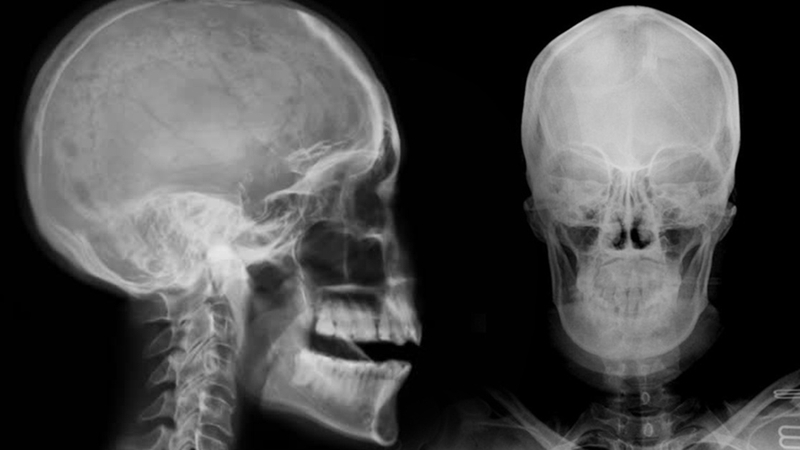

Chụp X-quang đầu là hình thức chẩn đoán hình ảnh giúp kiểm tra, đánh giá những vấn đề trong xương sọ, xương mặt và các bộ phận ở phần đầu. Đây là phương pháp khá dễ thực hiện, có kết quả nhanh, giúp kiểm tra, chẩn đoán và đánh giá các bệnh lý trên não bộ của bạn.

Chụp X-quang đầu thường được sử dụng trong các trường hợp té ngã, va đập mạnh vùng đầu, hoặc chấn thương do tai nạn giao thông. Kết quả chụp X-quang đầu có thể phản ánh được vùng xương sọ có bị tổn thương, rạn nứt hay bị vỡ. Ngoài ra, chụp X-quang đầu cũng giúp phát hiện kịp thời nếu có bị dị dạng cấu trúc vùng xương mặt, xương mũi, xương hàm. Nhờ đó, bác sĩ có thêm cơ sở để chẩn đoán cho từng trường hợp.

Chụp X-quang đầu cũng là phương pháp giúp chẩn đoán ung thư não. Tia X từ phương pháp này sẽ chiếu và cho thấy được những bất thường trong xương sọ do các khối u gây ra.